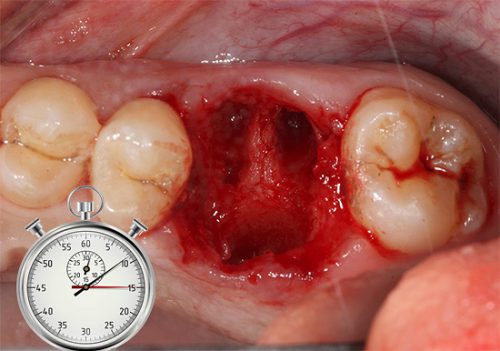

Если Вам удалили зуб, что делать в первые часы после операции – подробно расскажет врач. В течение некоторого времени после процедуры из лунки может течь кровь. Чтобы остановить кровотечение, необходимо наложить на пустую альвеолу ватный тампон, плотно прикусить его и подержать так в течение 45 минут.

Кровяной сгусток, образующийся на месте, где был зуб, важен для заживления, поэтому следует соблюдать меры осторожности, чтобы не травмировать его.

Как заживает лунка в десне

После вырывания зуба в десне остается полость, ее размеры зависят от типа зуба. Для заживления десны понадобится некоторое время.

- Кровотечение (при нормальном состоянии прекращается через 2-4 часа после процедуры).

Остановка кровотечения после операции

Раскачивание и извлечение зуба приводит к обильному кровотечению. Врач останавливает кровь сразу после операции с помощью стерильного отреза марли. Марлевый отрез кладут на кровоточащую лунку. Пациент должен крепко прикусить ткань. Чтобы надежно остановить кровь, не мешать образованию кровяного сгустка, нужно соблюдать простые правила:

Лунка в течение 20-30 минут после операции заполняется кровью, которая быстро сворачивается и образует плотный кровяной сгусток. Этот сгусток защищает рану от попадания грязи, микробов, бактерий и остатков еды.